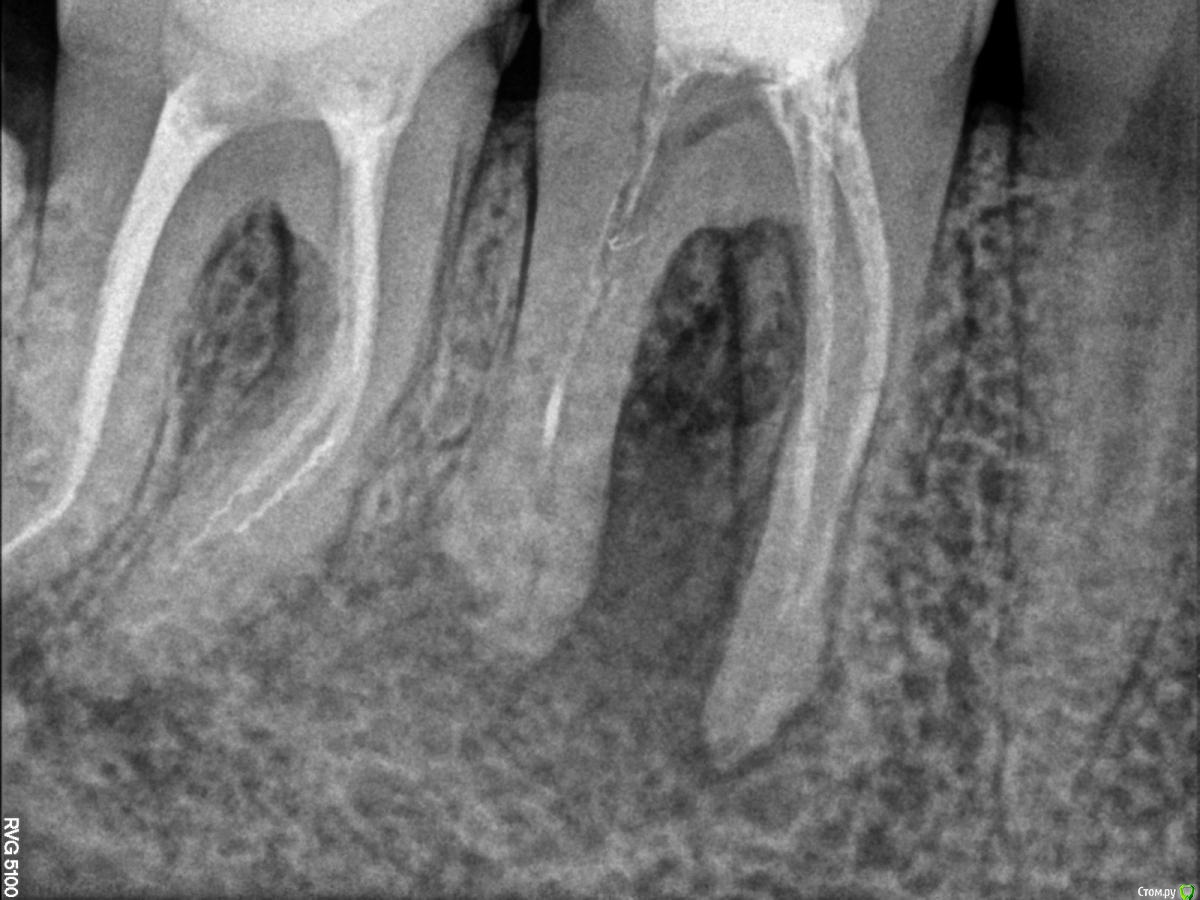

Bibika2020 Опубликовано 31 мая, 2020 Поделиться Опубликовано 31 мая, 2020 Всем добрый день. Предыстория:В 2018 году на зубе 46 откололся кусочек сзади и зуб начал сильно болеть. Зуб до этого был уже депульпирован лет 5-10 назад (уже не помню) и стоял со световой пломбой. В 2018 г. провели восстановление коронковой части зуба пломбой, в каналы не лазили.В 2019 году в районе этого зуба появился свищ, но зуб никак не беспокоил. Текущая ситуация:Весной 2020 года зуб начал реагировать на холодное и горячее и надкусывание средней степенью боли.Первое посещение врачаОбратился к врачу в марте (снимок 1 и 2). Доктор сказал, что можно попробовать перелечить каналы и сохранить зуб. Из трёх каналов один был не запломбирован, в двух других была гуттаперча. Доктор провела механическую и медикаментозную обработку двух каналов: незапломбированного и одного с гуттаперчей и заложила кальцийсодержащую пасту, поставила временную пломбу, выписала антибиотик 5 дней.Облегчение почувствовалось сразу. Через неделю свищ прошёл. Ещё через неделю опять появился. Второе посещение врачаКак раз подходило время очередного приёма, но доктор уже был другой в том же месте.Снимки 3 и 4. Доктор провела механическую и медикаментозную обработку двух каналов и заложила кальцийсодержащую пасту. Сказала, что временная пломба была сильно не герметична поэтому микробы попадали в зуб. Положила фум ленту и сделала световую пломбу 10 апреля. Свищ опять на какое-то время пропал и снова появился через пару недель. Третье посещение врачаНа следующем приёме доктор сделал снимок с гуттаперчей вставленной внутрь свища, на снимке гуттаперча дошла до низа левого канала, как раз того, который изначально не было запломбирован N лет назад (снимка, к сожалению, нет). Дальше подключился хирург и сказал, что такой зуб нужно удалять, т.к. гранулирующий периодонтит (если я правильно запомнил). Сейчас прошло почти 2 месяца есть неприятные ощущения от зуба и свищ то появляется, то пропадает. ВопросЗуб жалко удалять, на мой взгляд, он нормальный.Хотелось бы услышать мнение врачей, есть шанс сохранить зуб и что делать? Ссылка на комментарий

Kolchanov Опубликовано 1 июня, 2020 Поделиться Опубликовано 1 июня, 2020 Периодонтит. Причем еще соседний зуб может поддерживать процесс. Да и тот, которым сейчас занимаются.... Перелечивать надо всё, все каналы. Еще ощущение есть, глядя га снимок, что полость зуба так и не была раскрыта. Но это, конечно, надо "вживую" смотреть.По снимку зуб выглядит вполне достойным того, чтобы пробовать. А, если удалять, то еще и 7ку сразу, а то мало ли... Ссылка на комментарий

dok1 Опубликовано 1 июня, 2020 Поделиться Опубликовано 1 июня, 2020 Щестёрка с булавоообразным утолщением корня. Пошла резорбция апекса. Плюс резорбция в просвете каналов. Я в шестой неверю . По этому бы рекомендовал удалить. Седьмой, если удастся извлечь инструмент, можно вылечить Ссылка на комментарий